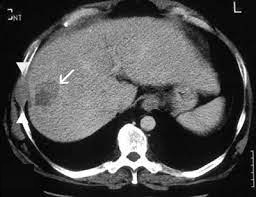

影像学:当发现一个微小病变时,如何区分良恶性?